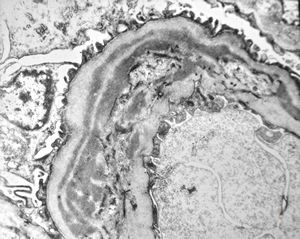

M,6y. | Alport syndrome- digital photo from the screen